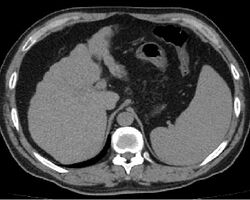

Imaging

Ultrasound is routinely used in the evaluation of cirrhosis.[36] It may show a small and shrunken liver in advanced disease. On ultrasound, there is increased echogenicity with irregular appearing areas.[54] Other suggestive findings are an enlarged caudate lobe, widening of the fissures and enlargement of the spleen.[55] An enlarged spleen, which normally measures less than 11–12 cm in adults, may suggest underlying portal hypertension.[56] Ultrasound may also screen for hepatocellular carcinoma and portal hypertension.[36] This is done by assessing flow in the hepatic vein.[57] An increased portal vein pulsatility may be seen. However, this may be a sign of elevated right atrial pressure.[58] Portal vein pulsatility are usually measured by a pulsatility indices (PI).[57] A number above a certain values indicates cirrhosis (see table below).

Other scans include CT of the abdomen and MRI.[36] A CT scan is non-invasive and may be helpful in the diagnosis.[36] Compared to the ultrasound, CT scans tend to be more expensive. MRI provides excellent evaluation; however, is a high expense.[36]

Liver cirrhosis on CT imaging of the abdomen in transverse view